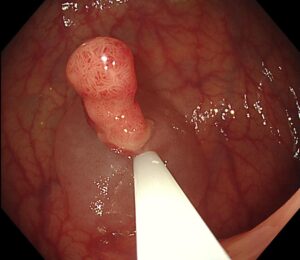

👉 生理食塩水をポリープの下に注入し(写真3)、 粘膜下層がふっくらと盛り上がりました(写真4)

(写真3)